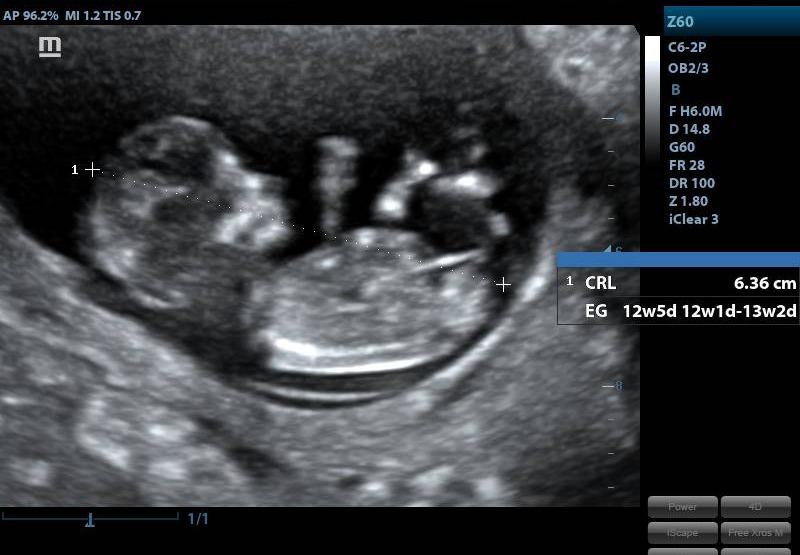

SCREENING DEL PRIMER TRIMESTRE

SERVICIOSCREENING DEL PRIMER TRIMESTRE

CONDICIÓNINDICACIONES: SE REALIZA ENTRE LAS 12 Y 13 SEMANAS CON 6 DIAS DE GESTACION.

ESPECIFICACIONESLONGITUD DEL FETO CORONOCAUDAL (LCC) LIQUIDO AMNIOTICO FRECUENCIA CARDIACA FETAL (LCF) DESCARTAR CROMOSOMOPATIAS MEDICION TRANSLUCENCIA NUCAL (TN) PRESENCIA Y MEDICION DE HUESO NASAL ANGULO MAXILOFACIAL PARTES FETALES DIAFRAGMA EVALUACION CAMARA CARDIACA EVALUACION COLUMNA VERTEBRAL FLUJOMETRIA DOPPLER ARTERIAS UTERINAS (PREVENTOR PREECLAMPSIA) DUCTUS VENOSO UBICACIÓN DE PLACENTA, DESCARTAR HEMATOMAS O DESPRENDIIENTOS INSERCION DE CORDON UMBILICAL